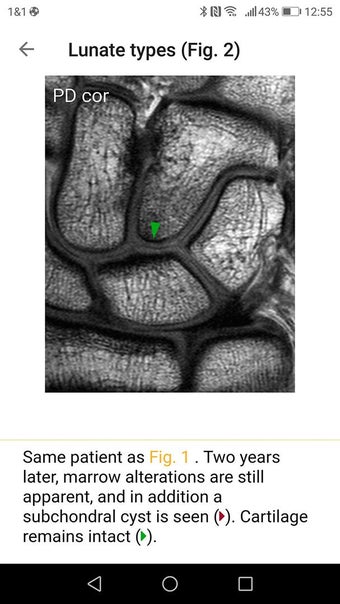

Die Pro-Version enthält mehr als 4.000 hochwertige Bilder von herausragender Bildqualität, die den Text veranschaulichen. Sie sind so konzipiert, dass sie dem Leser einen schnellen Überblick über die wichtigsten Informationen zum Zustand geben.